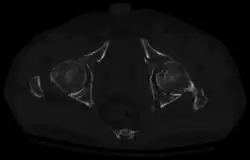

Axial CT image (viewed on bone windows) of a complex comminuted left acetabular fracture involving both anterior and posterior columns. -